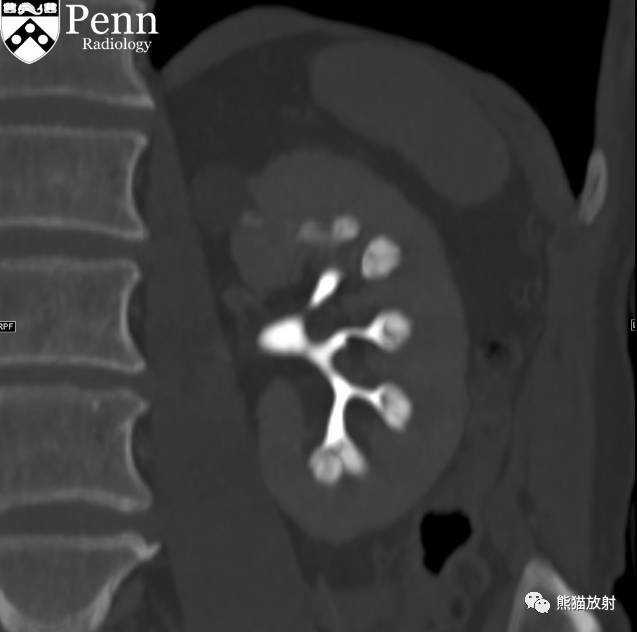

Scout, coronal precontrast, axial nephrographic/excretory phase images, and volume-rendered coronal reconstructions of the left and right kidneys are shown below.

定位像、冠状平扫、轴位排泄期图像及左、右肾冠状VR重建如下所示。

CT urogram (2017): Noncontrast images demonstrate multiple bilateral nonobstructing renal calculi, the largest measuring 6 mm in the right kidney. Some of the calcifications could represent nephrocalcinosis — for example, those in the upper pole of the right kidney. The kidneys show symmetric enhancement without suspicious renal mass. Multiple bilateral exophytic simple renal cysts are noted, the largest in the midpole of the right kidney measuring 3.6 x 4.3 cm. There are additional subcentimeter low-attenuation lesions that are too small to characterize. There is a “paintbrush sign” appearance to the renal medullae in keeping with a history of medullary sponge kidney. There is mild bladder wall thickening and trabeculation that may be related to chronic outlet obstruction. Further evaluation is deferred to cystoscopy.

CTU:CT平扫可见双肾多发非梗阻性肾结石,右肾最大者直径约6mm,其中一些钙化可能代表肾结石,例如,右肾上极的那些。肾脏对称性强化,未见可疑肾肿物。双肾可见多发单纯性肾囊肿,大者位于右肾中部,大小约3.6 x 4.3 cm;另可见不足1cm的低密度灶,其太小而不能显示。肾髓质表现为“毛刷征”,符合髓质海绵肾。膀胱壁轻度增厚并小梁形成,与慢性流出道梗阻有关。进一步评估需膀胱镜检查。